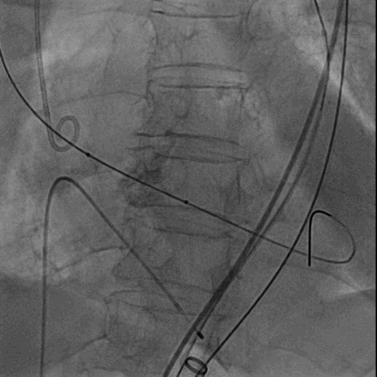

经右股静脉置入7F JR指引导管至下腔静脉,经右股动脉置入6F猪尾导管至腹主动脉,于下腔静脉及腹主动脉同时造影精确定位目标穿刺点。

穿刺系统与圈套器配合完成穿刺并建立下腔静脉至腹主动脉的通路

主动脉根部造影